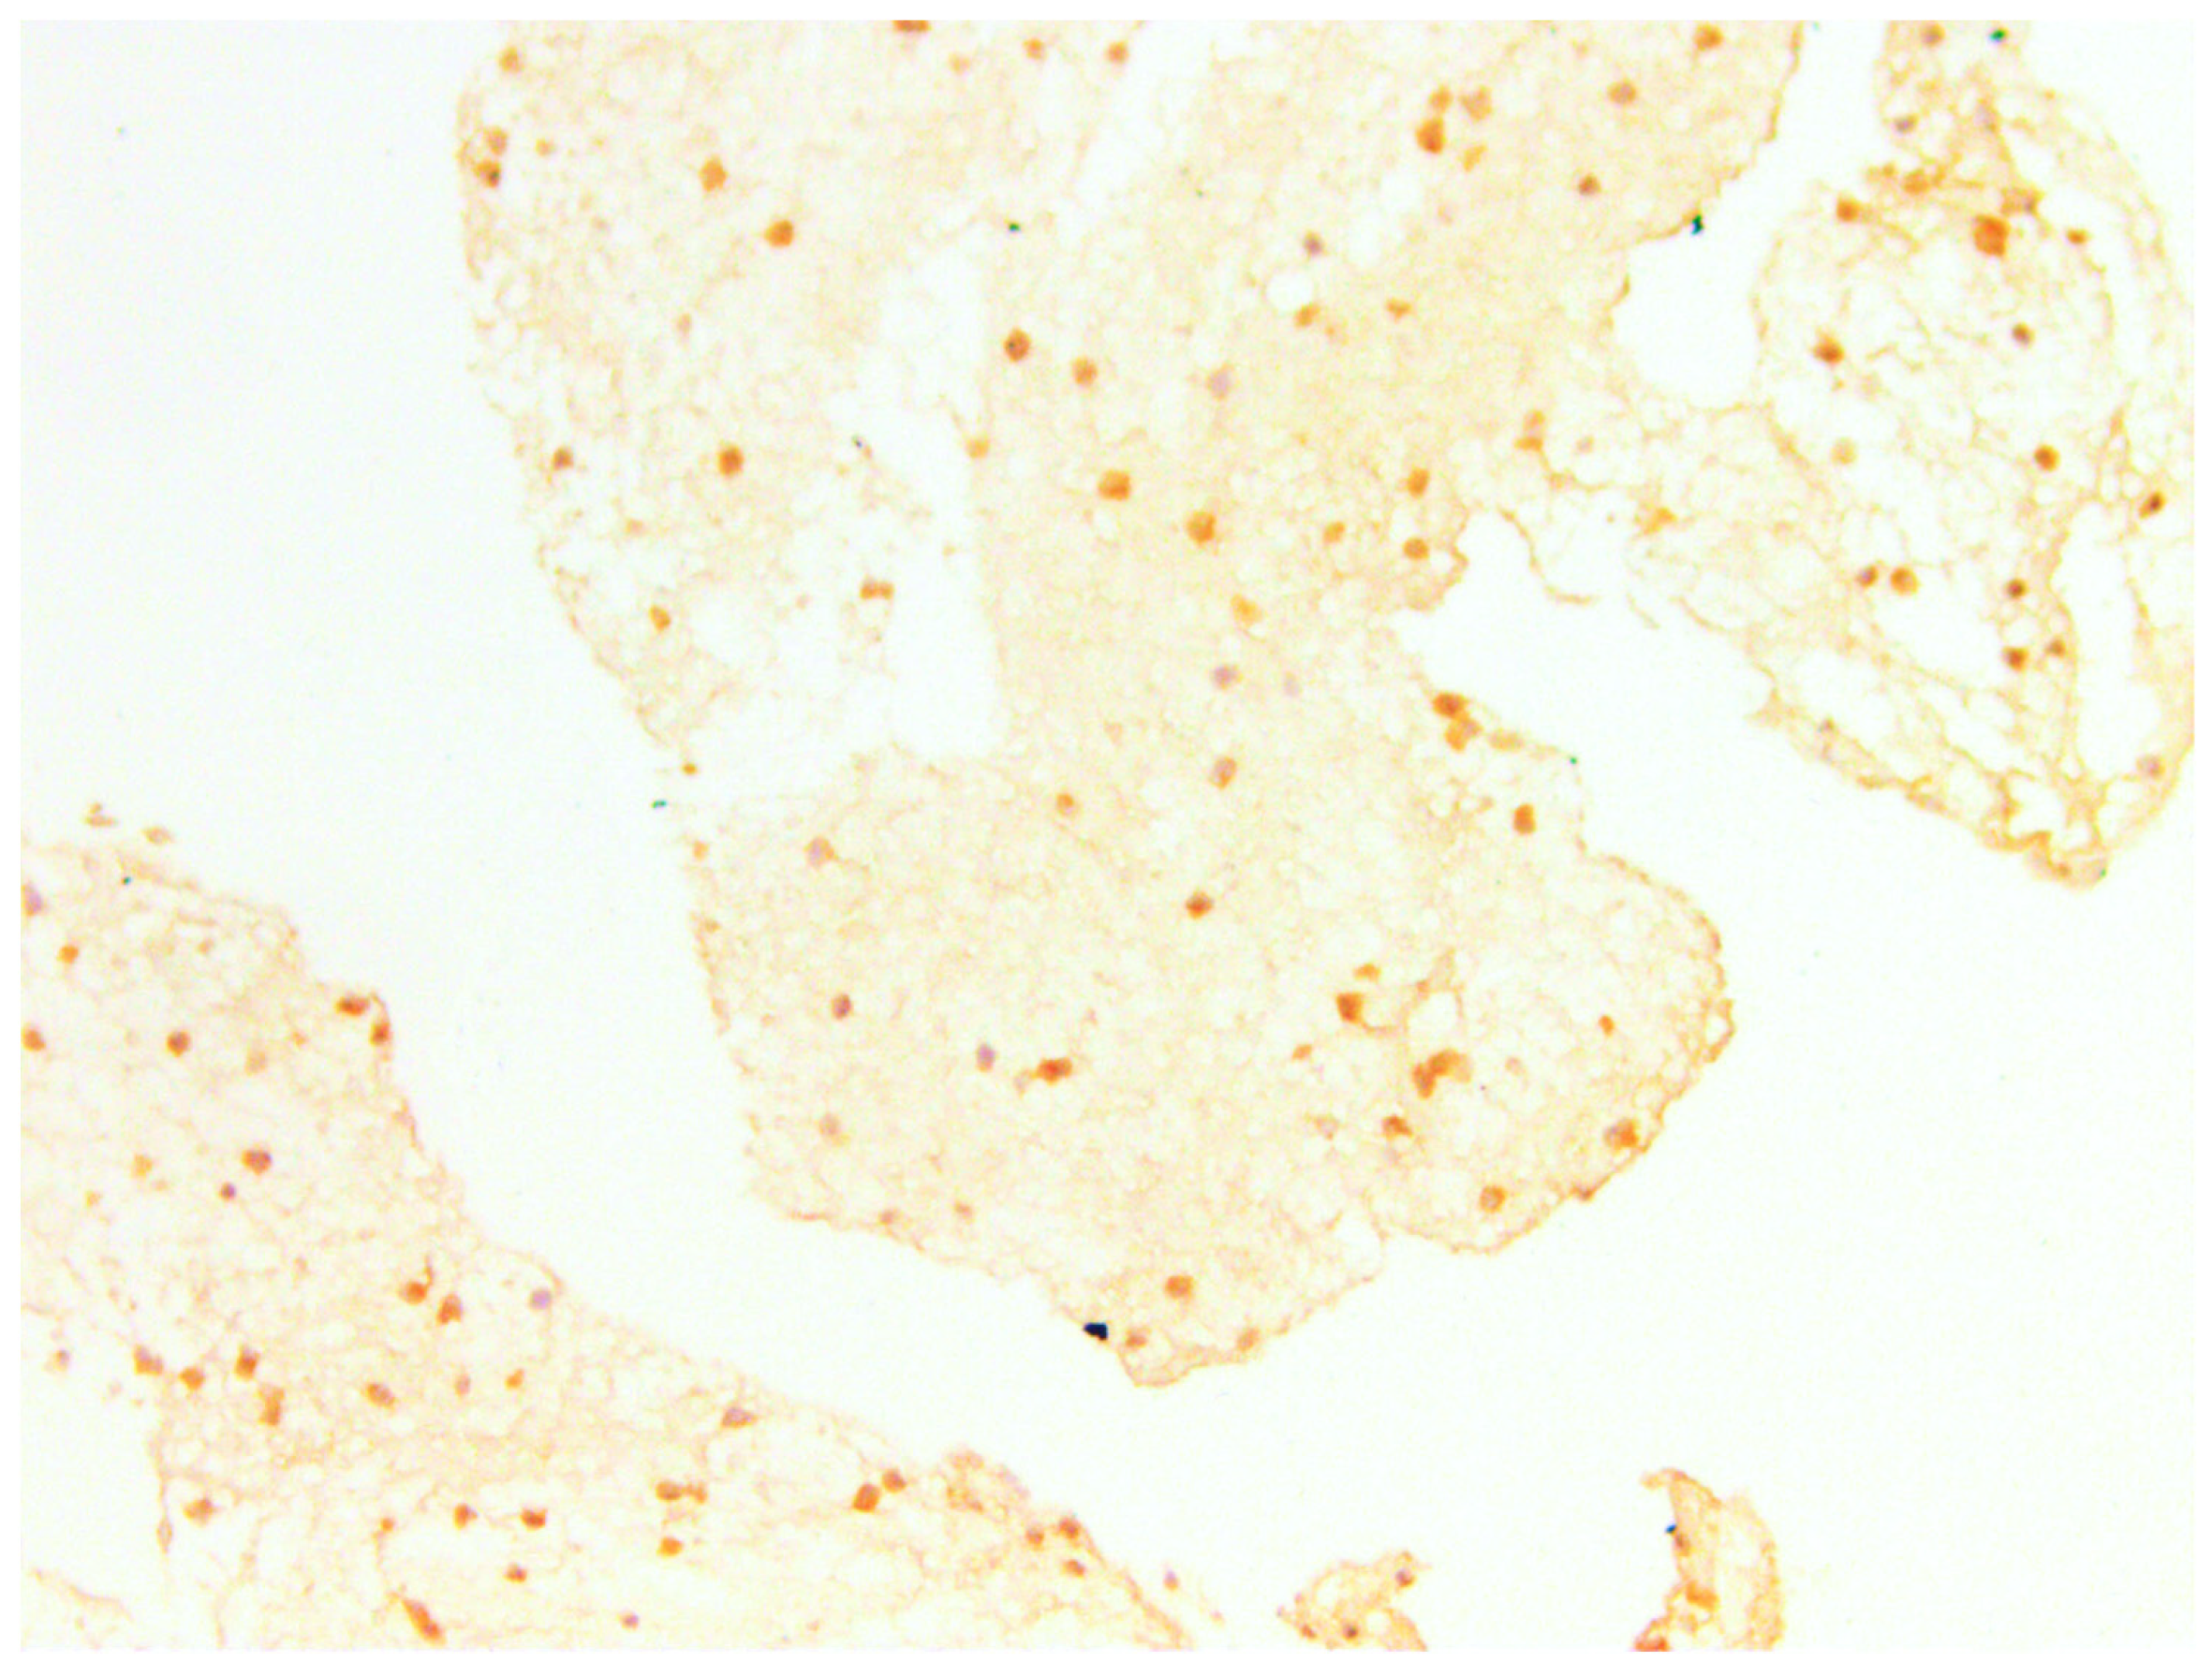

3.3.1. CD44

3.3.2. CD133

3.3.3. CD10